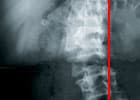

S-förmige oder C-förmige seitliche Verbiegung der WS (bei der Betrachtung von hinten) in Verbindung mit einer Verdrehung der WS in sich selbst (Torsion).

Jede Skoliose hat einen Hauptbogen, der wegen der Statik funktionelle Gegenbögen auslöst. Die Schwere der Skoliose wird nach der Krümmung des Hauptbogens eingeteilt. Danach richtet sich die Therapie.

Krümmungswinkel der Seitverbiegung:

unter 20°: Krankengymnastik

20° - 40°: Korsettversorgung in Kombination mit Krankengymnastik

über 40°: Operation